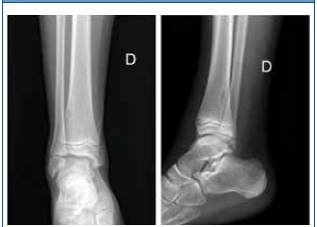

Paciente de 11 años que consulta por dolor en la extremidad inferior derecha tras un traumatismo contra el bordillo de una piscina. En la exploración física se observa edema y dolor intenso a la palpación en la zona pretibial a nivel distal. Mantiene un apoyo estable, con leve cojera para la deambulación. Se solicita una radiografía de tibia y peroné en la que se identifica una lesión lítica cortical ovalada de bordes esclerosos en la zona distal de la tibia derecha, compatible con defecto fibroso cortical (Fig. 1). Se indica un tratamiento conservador, presentando una evolución satisfactoria, con cese progresivo de la sintomatología.

Lesión lítica cortical ovalada y de borde escleroso en la metáfisis distal de la tibia derecha compatible con defecto fibroso cortical. Izquierda: proyección anteroposterior. Derecha: proyección lateral.